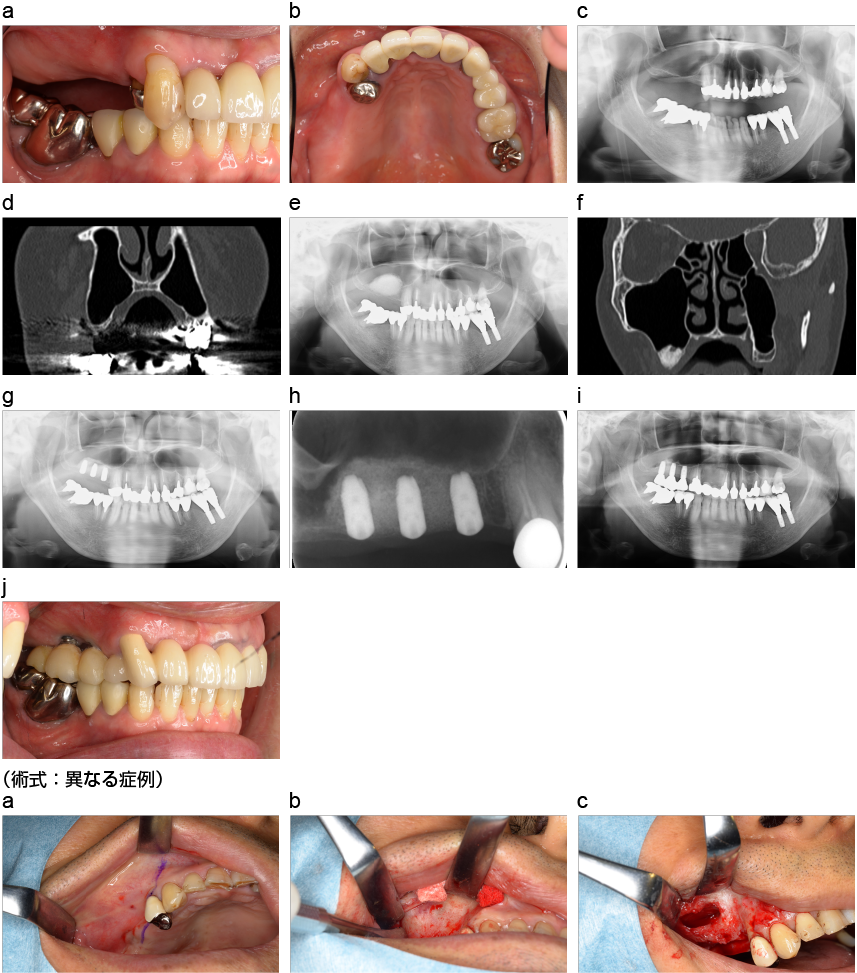

骨造成方法(上顎洞底挙上術)

上顎洞底挙上術(サイナスリフト)の術式。上顎臼歯部の不足した骨を造成する方法の1つで、よく用いられる。

a、b:術前の口腔内写真。

c:術前のレントゲン画像。

d:術前のCBCT画像。上顎洞が発達しており、インプラントを埋入するための骨がない。

e:人工骨移植後のレントゲン画像。

f:人工骨移植後のCBCT画像。

g:インプラント埋入後のレントゲン画像。

h:デンタルエックス線画像。

i:上部構造装着後のレントゲン画像。

j:上部構造装着後の口腔内写真。

(術式:異なる症例)

a:粘膜骨膜切開。

b:骨面を明示する。

c:骨削除し、上顎洞粘膜を丁寧に剥離し、挙上する。このスペースに移植骨、人工骨等を移植する。